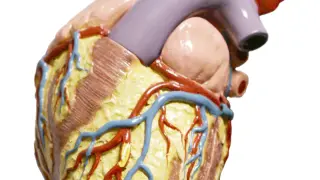

La sangre pobre en oxígeno desemboca en el corazón desde las dos venas cavas que drenan en la aurícula derecha. De allí, pasa al ventrículo derecho y, por la arteria pulmonar, la sangre es conducida a cada uno de ambos pulmones, donde se oxigena.

Después, las venas pulmonares culminan en la aurícula izquierda del corazón, desde donde pasa al ventrículo izquierdo y de allí se extiende, ya oxigenada, por la arteria aorta, al resto del cuerpo. Las arterias coronarias son básicas en todo el proceso para nutrir al músculo cardíaco de sangre rica en oxígeno.